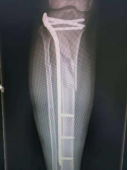

4.胫腓骨粉碎性骨折—MIPO技术